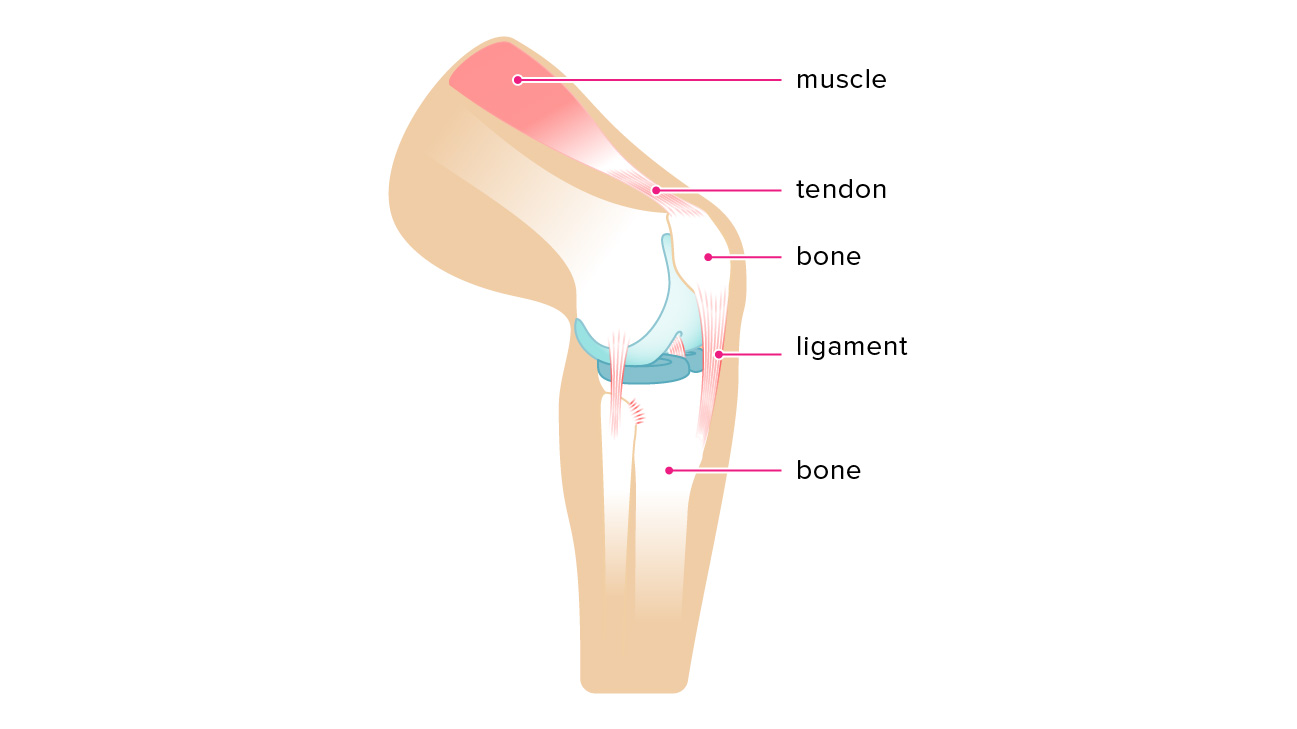

شما رباط ها و تاندون ها ی زیادی در بدن خود دارید. هر دو از بافت همبند ساخته شده اند و ممکن است پاره شوند یا بیش از حد کشیده شوند، اما از نظر عملکرد متفاوت هستند و برای مکانیک مناسب بدن ضروری هستند.

رباط ها و تاندون ها هر دو از بافت همبند فیبری تشکیل شده اند، اما شباهت در اینجا به پایان می رسد. رباط ها به صورت نوارهای متقاطع ظاهر می شوند که استخوان را به استخوان می چسبانند و به تثبیت مفاصل کمک می کنند. به عنوان مثال، رباط صلیبی قدامی (ACL) استخوان ران را به استخوان ساق پا متصل می کند و مفصل زانو را تثبیت می کند.

تاندون ها که در هر انتهای عضله قرار دارند، عضله را به استخوان متصل می کنند. تاندون ها در سرتاسر بدن، از سر و گردن تا پاها یافت می شوند. تاندون آشیل بزرگترین تاندون بدن است. ماهیچه ساق پا را به استخوان پاشنه می چسباند. تاندون های روتاتور کاف به چرخش شانه به جلو و عقب کمک می کنند.

رباط ها و تاندون ها چگونه کار می کنند؟

رباط ها و تاندون ها را می توان اینطور تعریف کرد. که رباطها را بهعنوان طناب با یک سری طنابهای سخت و در هم تنیده در نظر بگیرید که استخوانها را به هم متصل میکنند. رباط ها همچنین دارای الیاف الاستیک هستند که به مفصل اجازه حرکت می دهد، اما نه آنقدر که بیش از ظرفیت خود حرکت کند.

رباط ها و تاندون ها را می توان اینطور تعریف کرد. که تاندون ها نیز طناب های سختی هستند، اما قدرت آنها کمی بیشتر از رباط هاست. با انقباض عضله، تاندون متصل استخوان را به حرکت می کشاند. به این فکر کنید که وقتی آرنج خود را خم می کنید چه اتفاقی برای عضله دو سر شما می افتد. تاندونها همچنین به جذب برخی از ضربههایی که عضلات هنگام شروع فعالیت میدهند، کمک میکنند.

تصویر رباط ها و تاندون ها در مقایسه با هم